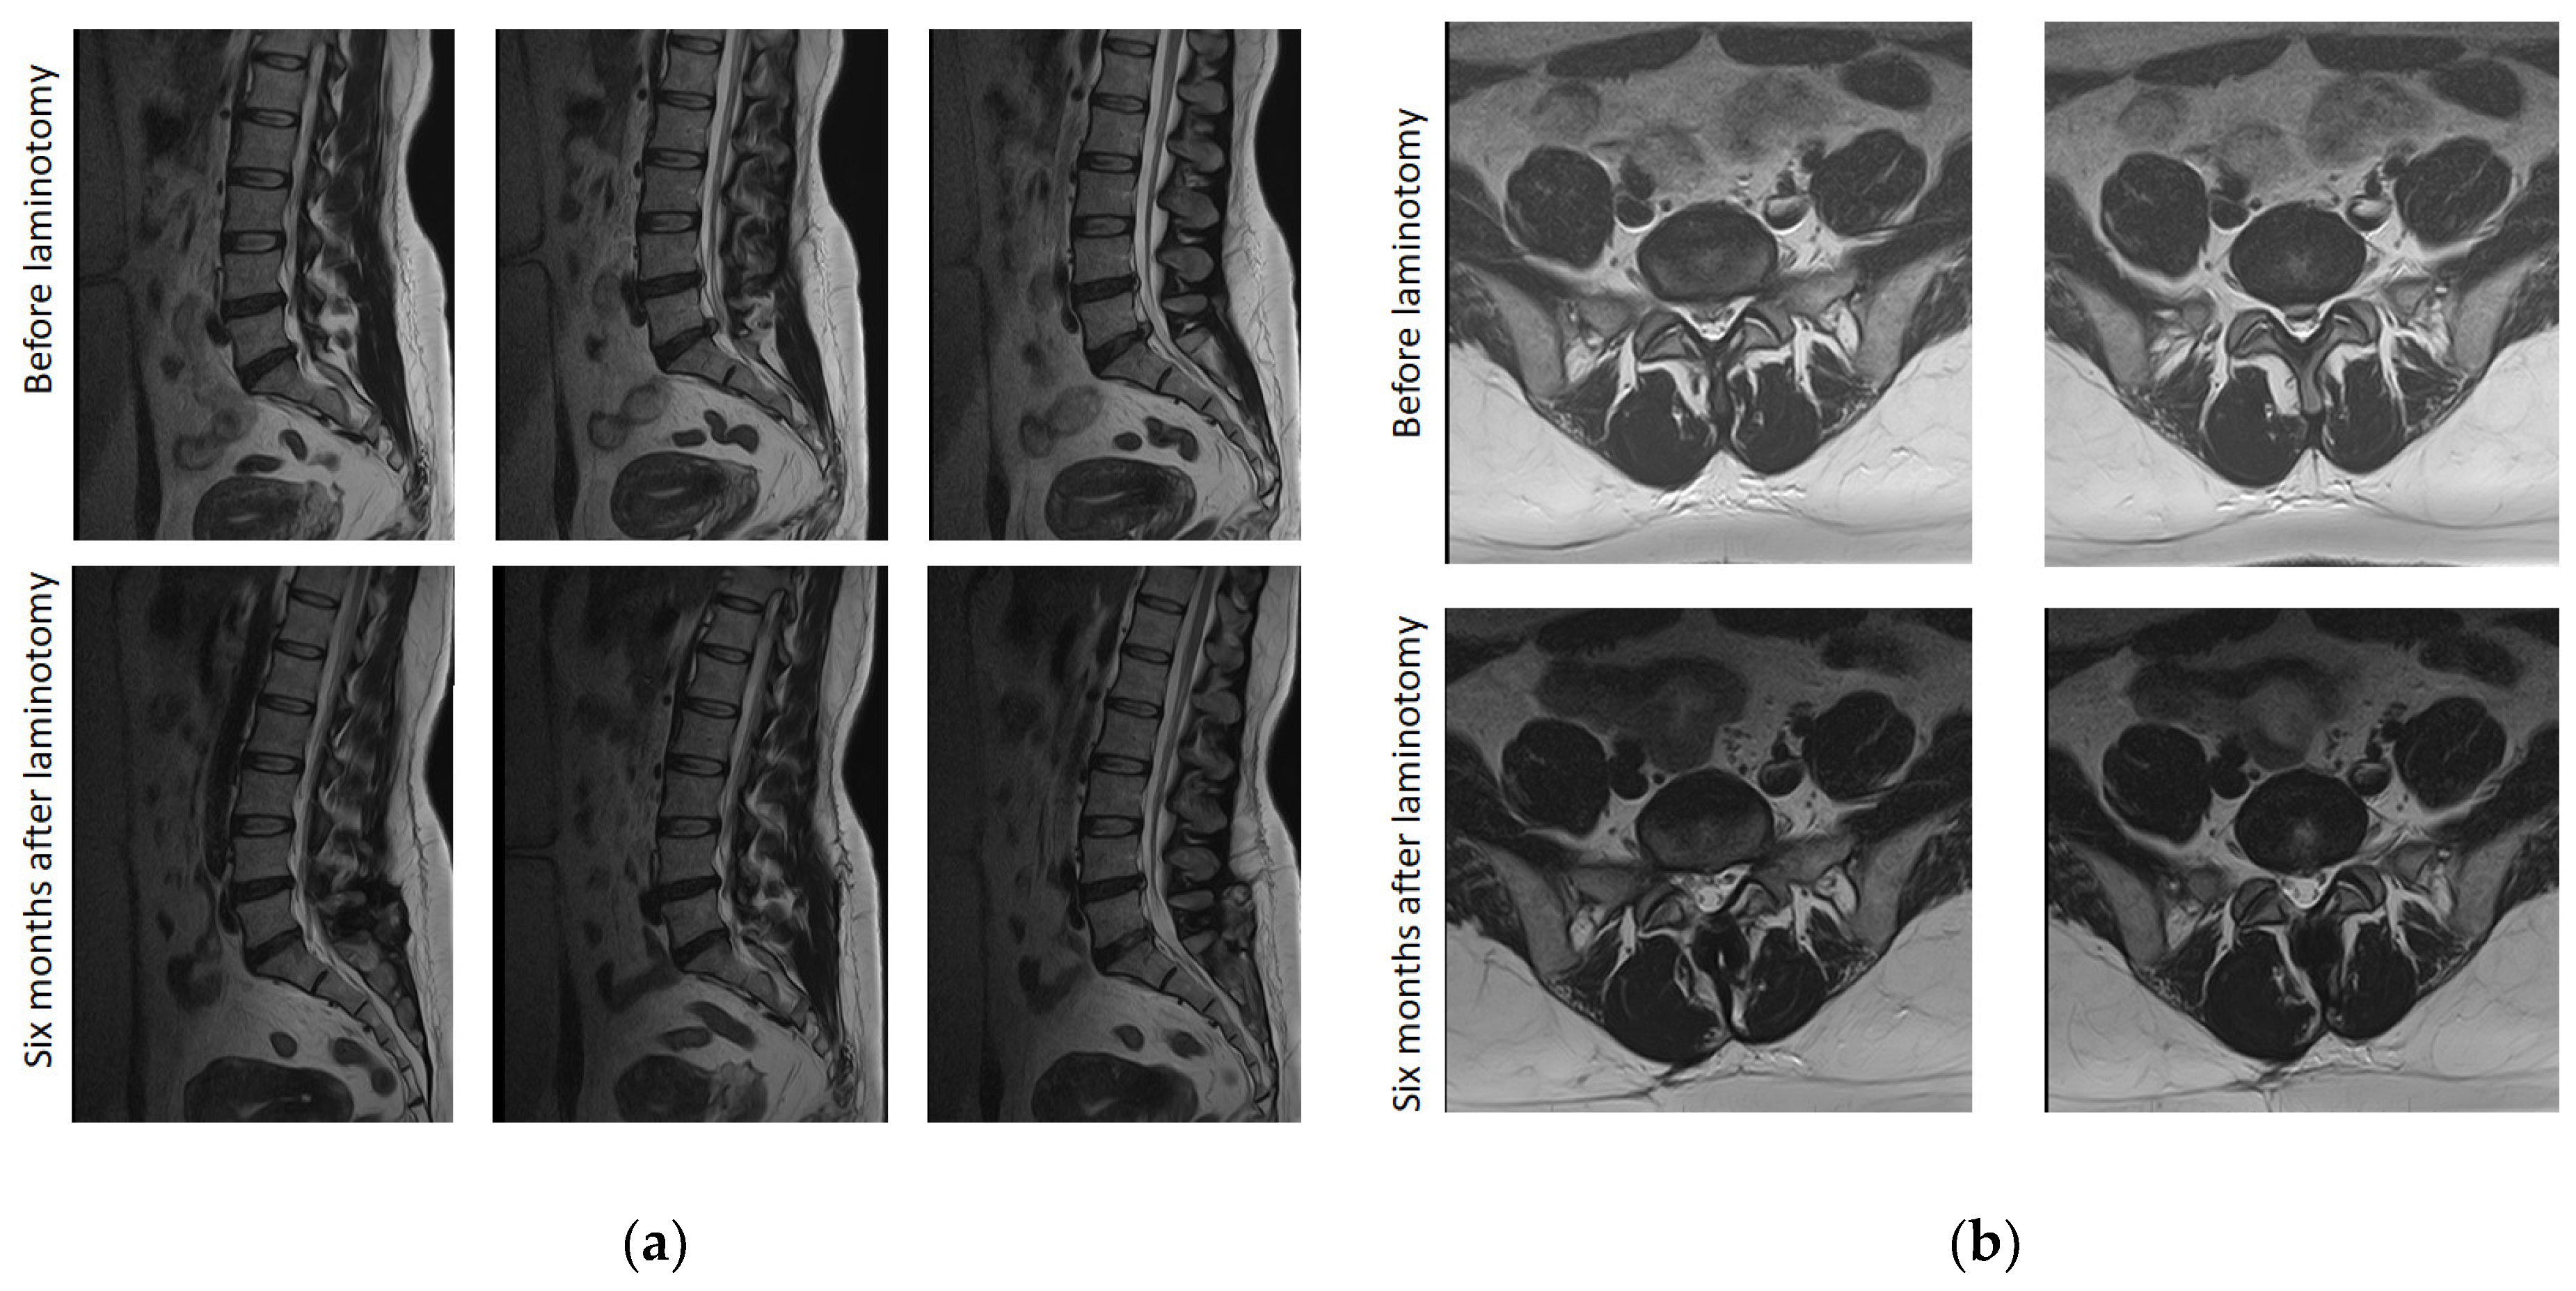

2.3.8. Magnetic Resonance Imaging Founds

3.8. Magnetic Resonance Imaging Examination